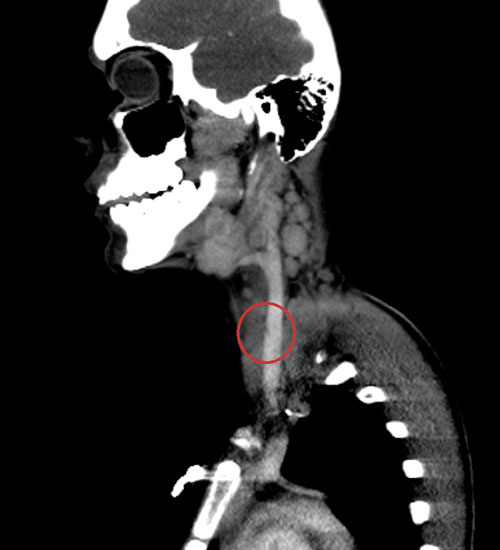

Fallbeskrivning God kunskap under hela vårdkedjan viktigt för att i tid väcka misstanke